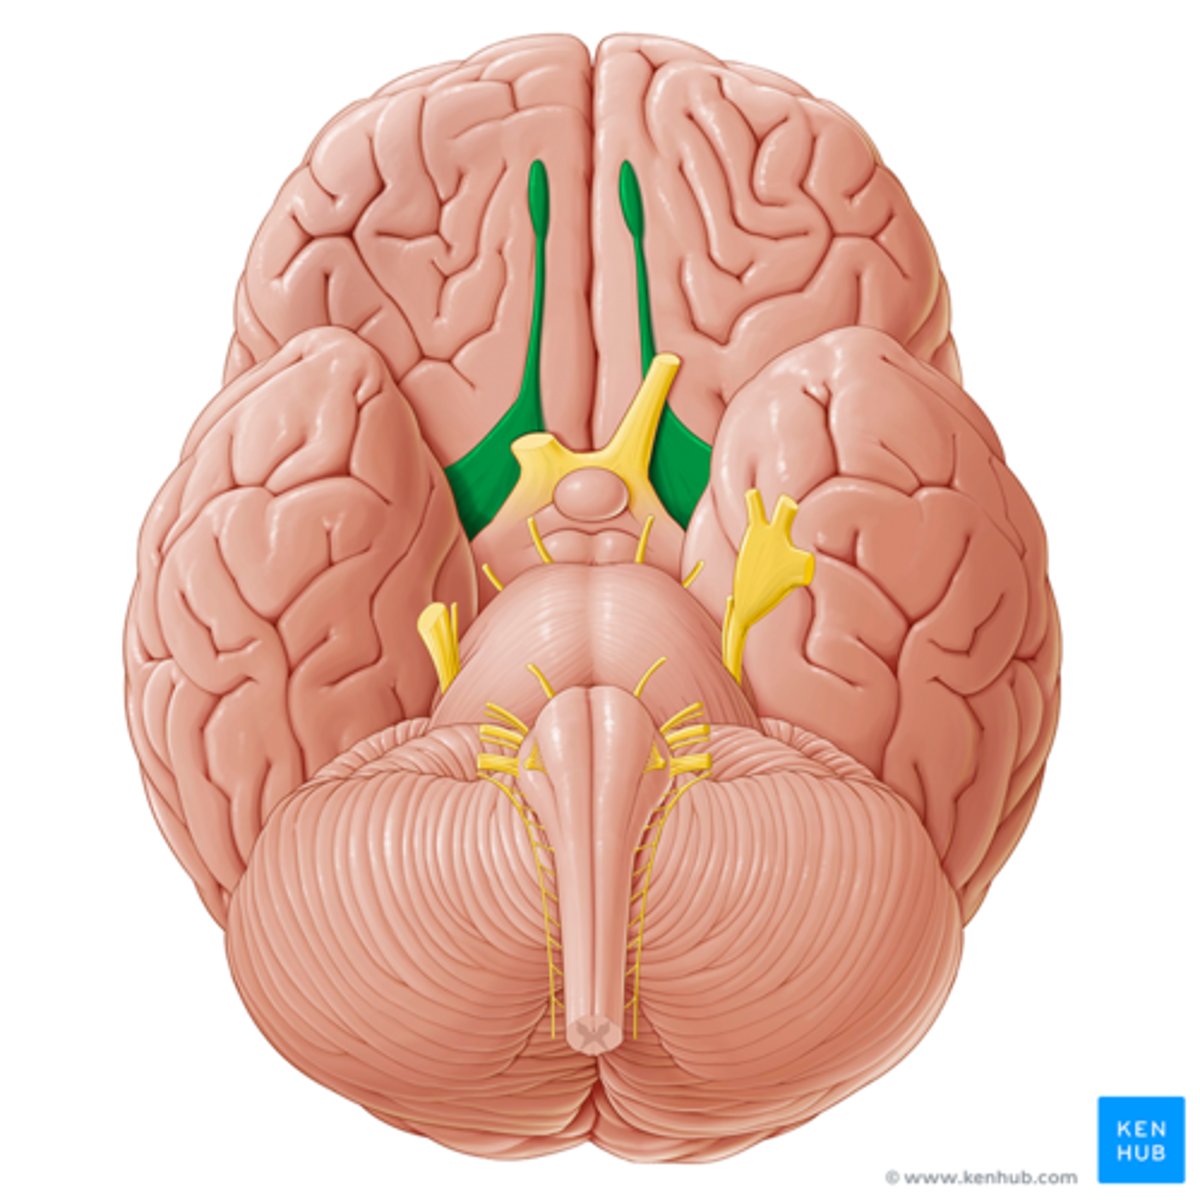

branches of olfactory nerve (cranial nerve I)

double check this

olfactory bulbs

olfactory tracts

double check this

optic nerves (cranial nerve II)

optic chiasma

optic tracts